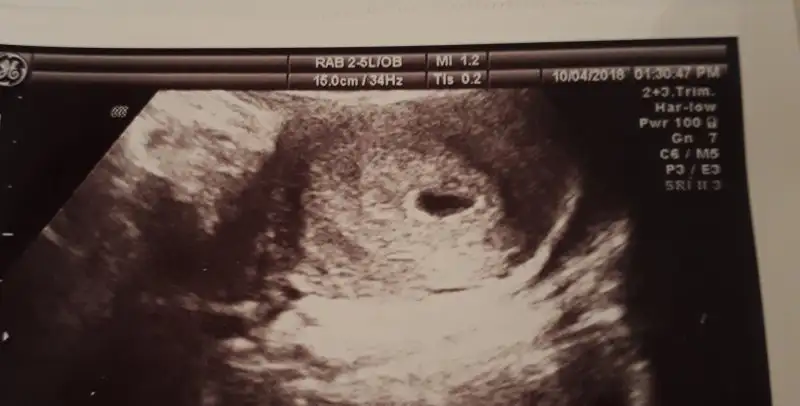

aynen canim çok kotuydum sayende şimdi gayet iyiyim. canim ben bakiyomda herkezde googda 5 yada 6 haftalik kese resimleri diye herkezde usteki CM si benimkinden kucuk 4.5 6.3 fln mesela ama benimki CM 15.0 bu ne ki bi bak, allahtan eşim nasil kolay resim yuklicegimi anlatti

15 cm diyor ama 15 cm kese bebekte olmazki valla bende anlamadım canım doktoruna sorsaydınya bi. Ama bi sorun olsaydı söylerdi bence.